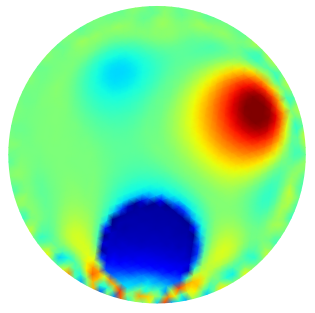

| GT | PGM-TV- | PGM-TV | |

|---|---|---|---|

|

|

|

|

| FN=0.0 % | PSNR=26.10 | PSNR=25.21 | |

|

|

|

|

| FN=0.62 % | PSNR=23.1918 | PSNR=23.044 | |

|

|

|

|

| FN=0.0 % | PSNR=26.999 | PSNR=24.6806 |

We finally evaluate the robustness against measurements corrupted by additive noise. The measured voltage is computed by the forward model KTCFwd and recorded as a vector . According to the degradation model (1), the noiseless measures are corrupted by additive white Gaussian noise to simulate experimentally measured voltages, with noise level :

| (47) |

The Signal to Noise Ratio (SNR) in dB is calculated as , while Peak-SNR (PSNR) will be used to measure the quality of an image after the reconstruction.

In Fig.5 some conductivity reconstructions are illustrated. The collected voltage has been corrupted by adding a realization of random noise with Gaussian distribution and noise level (added noise is such that the intrinsic SNR is 40dB). We observe that, even though the Oracle-Net was trained on noiseless data, the mask obtained in inference with noise measurements - Fig.5 first column - is sufficiently accurate, and PGM algorithm performs very well on the noise measurements. A natural consequence of having noise-corrupted measurements is the degradation in the conductivity reconstruction. Comparing the results in the third columns of Fig.4 and Fig.5 we observe quantitatively a degradation in the performance of reconstructions in terms of PSNR values. Analogous behavior can be observed comparing the fourth columns of Fig. 4 and Fig. 5, which have been obtained without taking advantage of the contribution of the Oracle Mask.